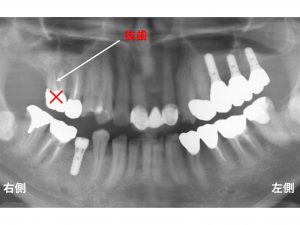

他にも問題がありました。

上顎右側の奥歯が痛みがありました。

根が折れていたのです。

歯根破折 です。

なぜ歯根破折 してしまったのでしょうか?

理由はいくつか考えられます。

一つ目は、

神経がないことです。

神経のない歯は、脆く、折れることがあります。

このブログでもよく解説する話です。

二つ目は、

歯がない部分が多いことです。

奥歯が多く欠損しているため、

どうしても残っている歯に負担が加わりやすくなってします。

他にも歯根破折 原因は考えられますが、

大きな原因としては、

上記の2つが考えられます。

痛みもあるため、

この歯は、抜歯 となります。